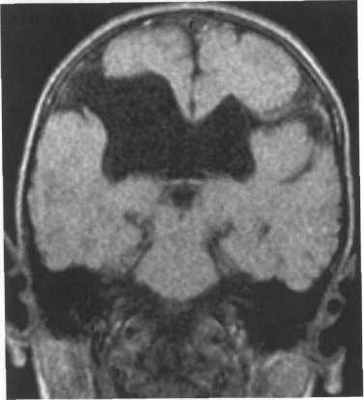

Субкортикальная групповая гетеротопия («двойная кора»):

(б) Коронарный срез: в этом же случае имеется расширение желудочков преимущественно спереди.

Кроме того, была проведена магнитно-резонансная томография головного мозга (аппарат Hitachi Airis Mate 0,2 Тесла), согласно которой на аксиальных срезах определялись билатеральные лентовидные зоны, соответствующие серому веществу головного мозга, расположенные преимущественно субкортикально. Изгибы гетеротопированных слоев повторяли основную складчатость кортикальной поверхности. На коронарных срезах подтверждалось субкортикальное расположение гетеротопированных зон. В коре видимых диспластических изменений не отмечено. Таким образом, можно утверждать о наличии у пациентки МР-признаков билатеральной ламинарной гетеротопии серого вещества, что характерно для синдрома «двойной коры» (рис. 2).

Рис. 3.21. Лентовидная гетеротопия. МРТ.

а - IR ИП, аксиальная плоскость; б - Т2-ВИ, аксиальная плоскость.

Полоса гетеротопированного серого вещества отделена

слоем белого вещества от коры и желудочков мозга.